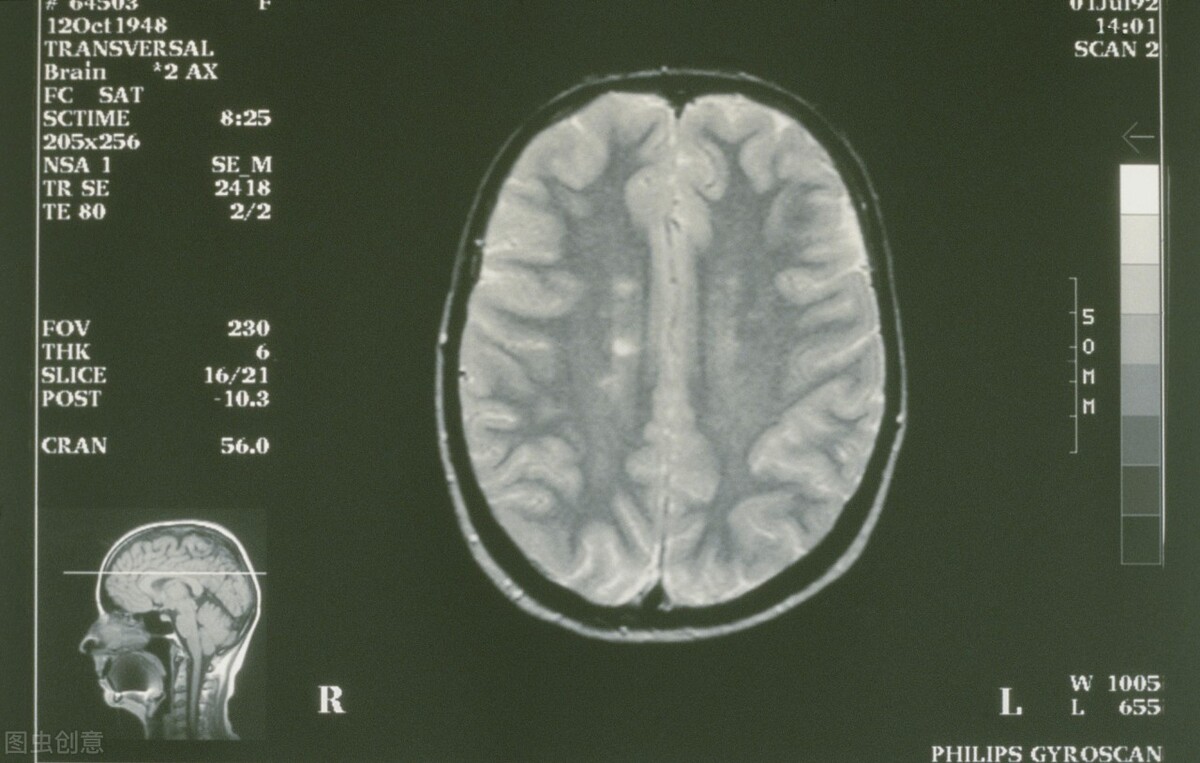

三、生理性脑萎缩。

很多人一看脑萎缩出现了,就害怕了,难道就是奔着老年痴呆去吗?

先别着急,脑萎缩并不一定都是严重的问题,很有可能是生理性的,换句话说就是正常现象。

你能抵抗衰老吗?能永葆青春吗?答案是否定的。

人势必要衰老,身体上的每一个器官和组织都会面临衰老,大脑也不例外。

大脑的衰老方式其实有很多,其中重要的一点,就是可以明显发现大脑萎缩。

在脑CT,或者颅脑核磁共振中可以看到,脑组织一点一点变小,这种萎缩通常都是比较正常的现象。

而且即使出现脑萎缩,很多人并没有什么感觉,也没有什么症状,仅仅是在体检中发现而已,对于这种情况并不需要太过担心,这是非常正常的现象。

可是,如果是阿尔兹海默症患者就该值得关注了,具体的治疗还是应该重视医生的建议。